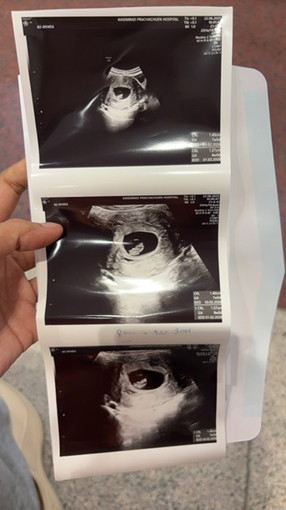

อัลตราซาวด์ค่ะ

อยากเห็นภาพแม่ๆตอนอัลตราซาวด์กันครั้งแรกค่ะ แล้วครั้งแรกตอนกี่วีคคะ

อันนี้ตอน8สัปดา5วัน